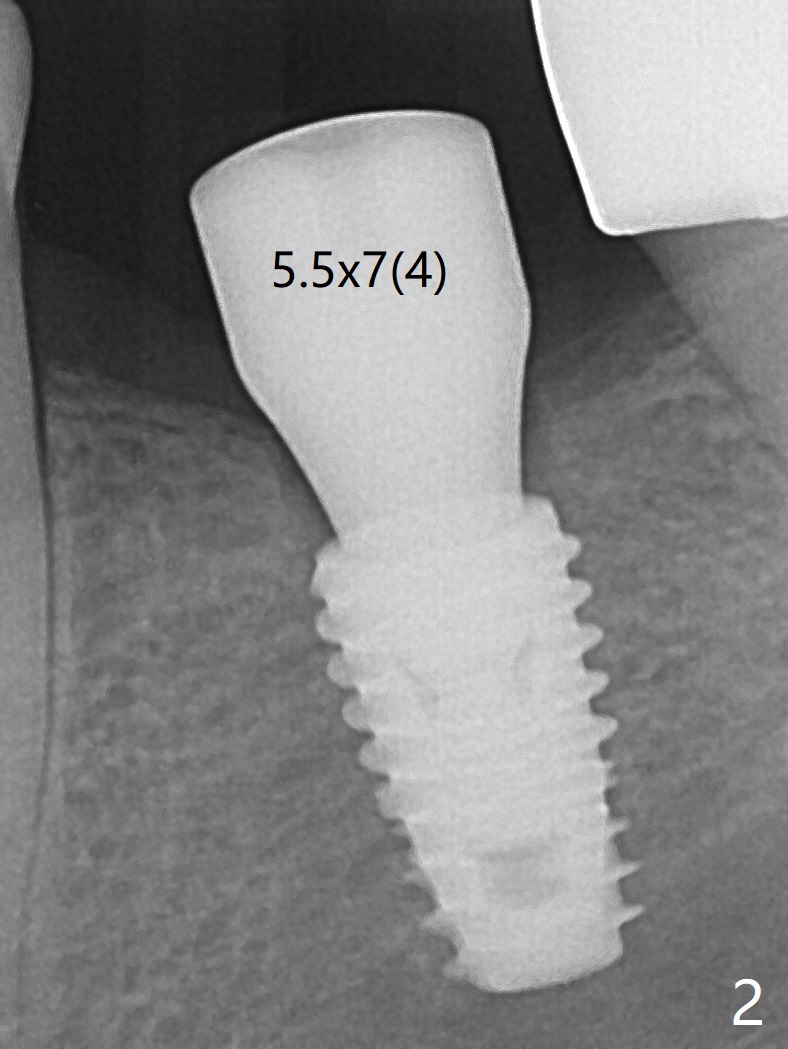

With one carpule of Xylocaine (34 mg with 17 mcg of Epinephrine), a 5x8.5 mm implant is placed at #19 in a timely and painless manner. The patient is pleased as compared to her previous implant placement at #3 and 30. Due to the thin buccal bone, the implant is placed ~.5 mm deeper than designed; a 6.5x4(2) mm healing abutment is incompletely seated (Fig.1). A smaller and skinny one (5.5x7(4) mm) is seated normally (Fig.2). Regional panoramic X-ray shows clearance from the Inferior Alveolar Canal (Fig.3 *). Although there is crestal bone resorption 6 months postop, the bone density next to the 1st thread is high (Fig.4 >). A 5.5x4(4) mm cemented abutment is placed for impression. The patient returns with #18 crown dislodgement and #19 crown loosening 11 months post cementation (Fig.5 <: gap between implant and abutment). Since the crown and abutment are unable to be torqued properly, they are removed (Fig.6). A narrower abutment is able to be seated apparently completely while a metal post (Fig.7 *) is tried in in the distal root of #18. To reduce the chance of re-fracture of #18 crown, the tooth #15 needs to be distalized orthodontically so that an implant will be placed at #14 (Fig.5).